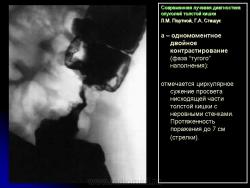

В 1961 г. Wellin предложил методику рентгенологического исследования толстой кишки, названную автором одномоментным двойным контрастированием толстой кишки (ОДКТК). Основное отличие ее от классической ирригоскопии состоит в том, что для исследования толстой кишки используется значительно меньшее количество бариевой взвеси и сразу же, по мере ее введения в дистальные отделы кишки, дальнейшее продвижение осуществляется специальным одноразовым устройством с помощью воздуха, вводимого под контролем рентгенотелевидения с учетом клинических особенностей пациента. Опыт многих исследователей и наш личный опыт указывают, что такие предосторожности при исследовании обусловлены не возможностью осложнений, а тем, что нередко быстрое контрастирование кишки может вызвать спазм отдельных ее участков и тем самым уменьшить его эффективность. Как правило, для исследования всех отделов толстой кишки, так же как и приирригоскопии, применяется стандартизованная методика с использованием тех же пяти проекций. Фиксация изображения осуществляется на рентгеновскую пленку средних размеров 18 х 24, 24 х 30 см. Основными достоинствами ОДКТК следует считать его высокую диагностическую эффективность, методическую простоту и возможность использования при скрининговых обследованиях групп риска по раку толстой кишки. В ОДКТК удачно сочетаются фазы “тугого” наполнения и двойного контрастирования – основные элементы, позволяющие фиксировать внутристеночную инфильтрацию кишки в ее начальных проявлениях с помощью определения состояния контура кишки и толщины стенки. Двойное контрастирование позволяет получить исчерпывающую информацию о слизистой кишки, которая при отсутствии в ней изменений (небольших полиповидных образований, изъязвлений и др.) должна быть полностью разглажена и лишена складчатости (рис. 1).

В 1961 г. Wellin предложил методику рентгенологического исследования толстой кишки, названную автором одномоментным двойным контрастированием толстой кишки (ОДКТК). Основное отличие ее от классической ирригоскопии состоит в том, что для исследования толстой кишки используется значительно меньшее количество бариевой взвеси и сразу же, по мере ее введения в дистальные отделы кишки, дальнейшее продвижение осуществляется специальным одноразовым устройством с помощью воздуха, вводимого под контролем рентгенотелевидения с учетом клинических особенностей пациента. Опыт многих исследователей и наш личный опыт указывают, что такие предосторожности при исследовании обусловлены не возможностью осложнений, а тем, что нередко быстрое контрастирование кишки может вызвать спазм отдельных ее участков и тем самым уменьшить его эффективность. Как правило, для исследования всех отделов толстой кишки, так же как и приирригоскопии, применяется стандартизованная методика с использованием тех же пяти проекций. Фиксация изображения осуществляется на рентгеновскую пленку средних размеров 18 х 24, 24 х 30 см. Основными достоинствами ОДКТК следует считать его высокую диагностическую эффективность, методическую простоту и возможность использования при скрининговых обследованиях групп риска по раку толстой кишки. В ОДКТК удачно сочетаются фазы “тугого” наполнения и двойного контрастирования – основные элементы, позволяющие фиксировать внутристеночную инфильтрацию кишки в ее начальных проявлениях с помощью определения состояния контура кишки и толщины стенки. Двойное контрастирование позволяет получить исчерпывающую информацию о слизистой кишки, которая при отсутствии в ней изменений (небольших полиповидных образований, изъязвлений и др.) должна быть полностью разглажена и лишена складчатости (рис. 1).

В 1961 г. Wellin предложил методику рентгенологического исследования толстой кишки, названную автором одномоментным двойным контрастированием толстой кишки (ОДКТК). Основное отличие ее от классической ирригоскопии состоит в том, что для исследования толстой кишки используется значительно меньшее количество бариевой взвеси и сразу же, по мере ее введения в дистальные отделы кишки, дальнейшее продвижение осуществляется специальным одноразовым устройством с помощью воздуха, вводимого под контролем рентгенотелевидения с учетом клинических особенностей пациента. Опыт многих исследователей и наш личный опыт указывают, что такие предосторожности при исследовании обусловлены не возможностью осложнений, а тем, что нередко быстрое контрастирование кишки может вызвать спазм отдельных ее участков и тем самым уменьшить его эффективность. Как правило, для исследования всех отделов толстой кишки, так же как и приирригоскопии, применяется стандартизованная методика с использованием тех же пяти проекций. Фиксация изображения осуществляется на рентгеновскую пленку средних размеров 18 х 24, 24 х 30 см. Основными достоинствами ОДКТК следует считать его высокую диагностическую эффективность, методическую простоту и возможность использования при скрининговых обследованиях групп риска по раку толстой кишки. В ОДКТК удачно сочетаются фазы “тугого” наполнения и двойного контрастирования – основные элементы, позволяющие фиксировать внутристеночную инфильтрацию кишки в ее начальных проявлениях с помощью определения состояния контура кишки и толщины стенки. Двойное контрастирование позволяет получить исчерпывающую информацию о слизистой кишки, которая при отсутствии в ней изменений (небольших полиповидных образований, изъязвлений и др.) должна быть полностью разглажена и лишена складчатости (рис. 1).